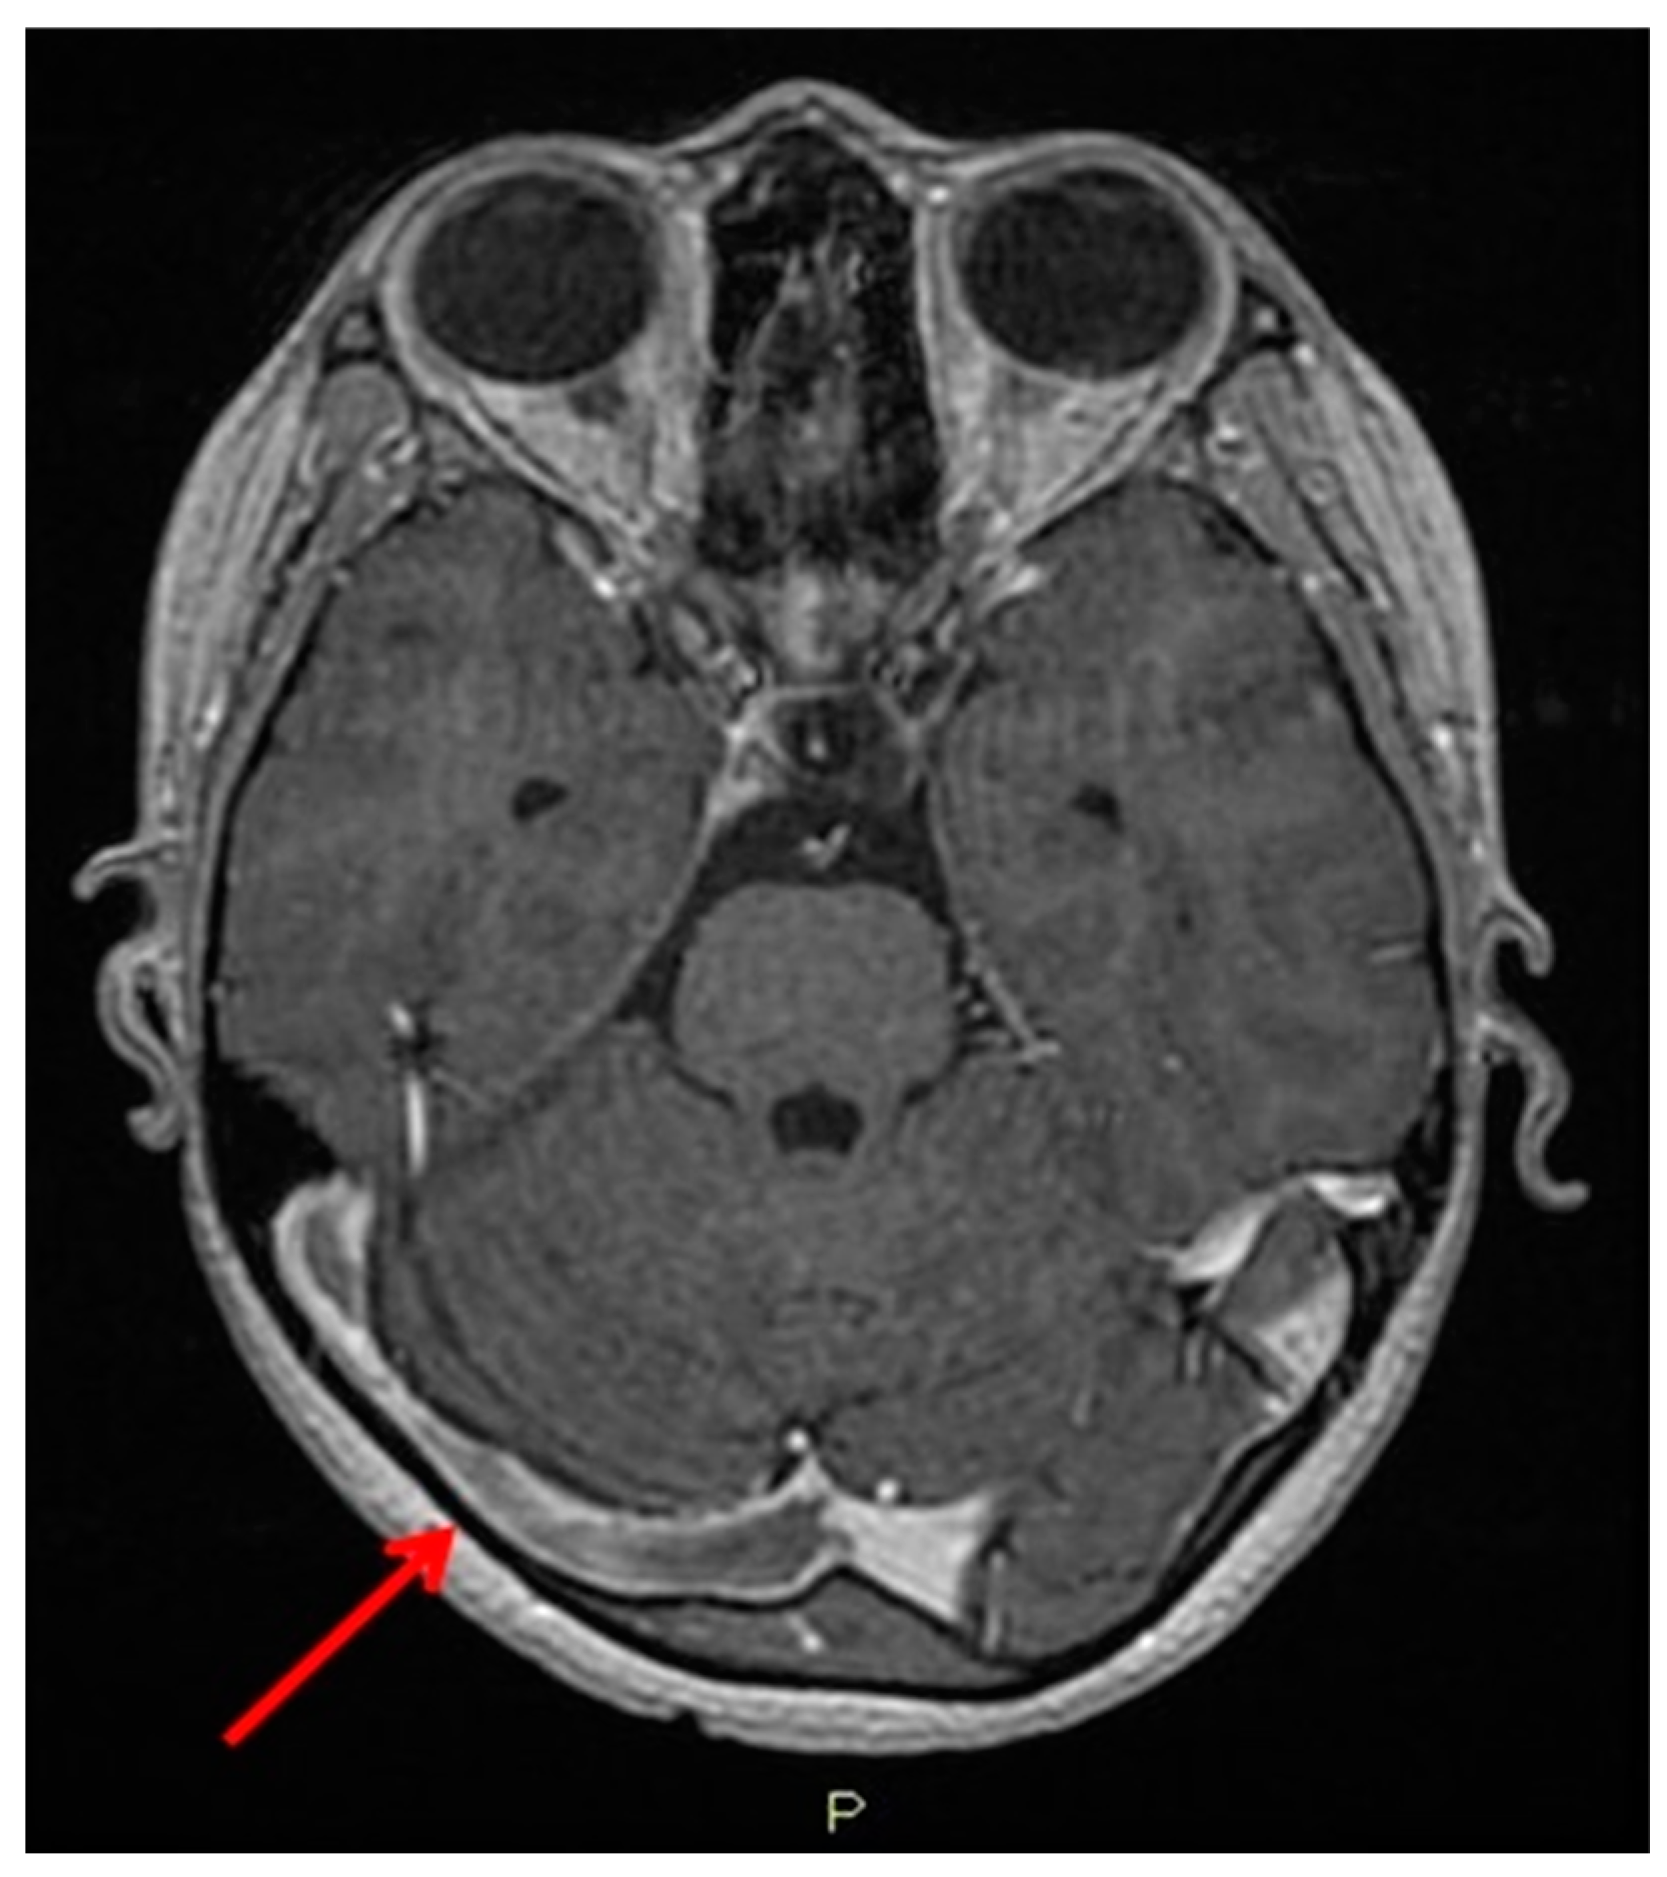

2. Case Presentation